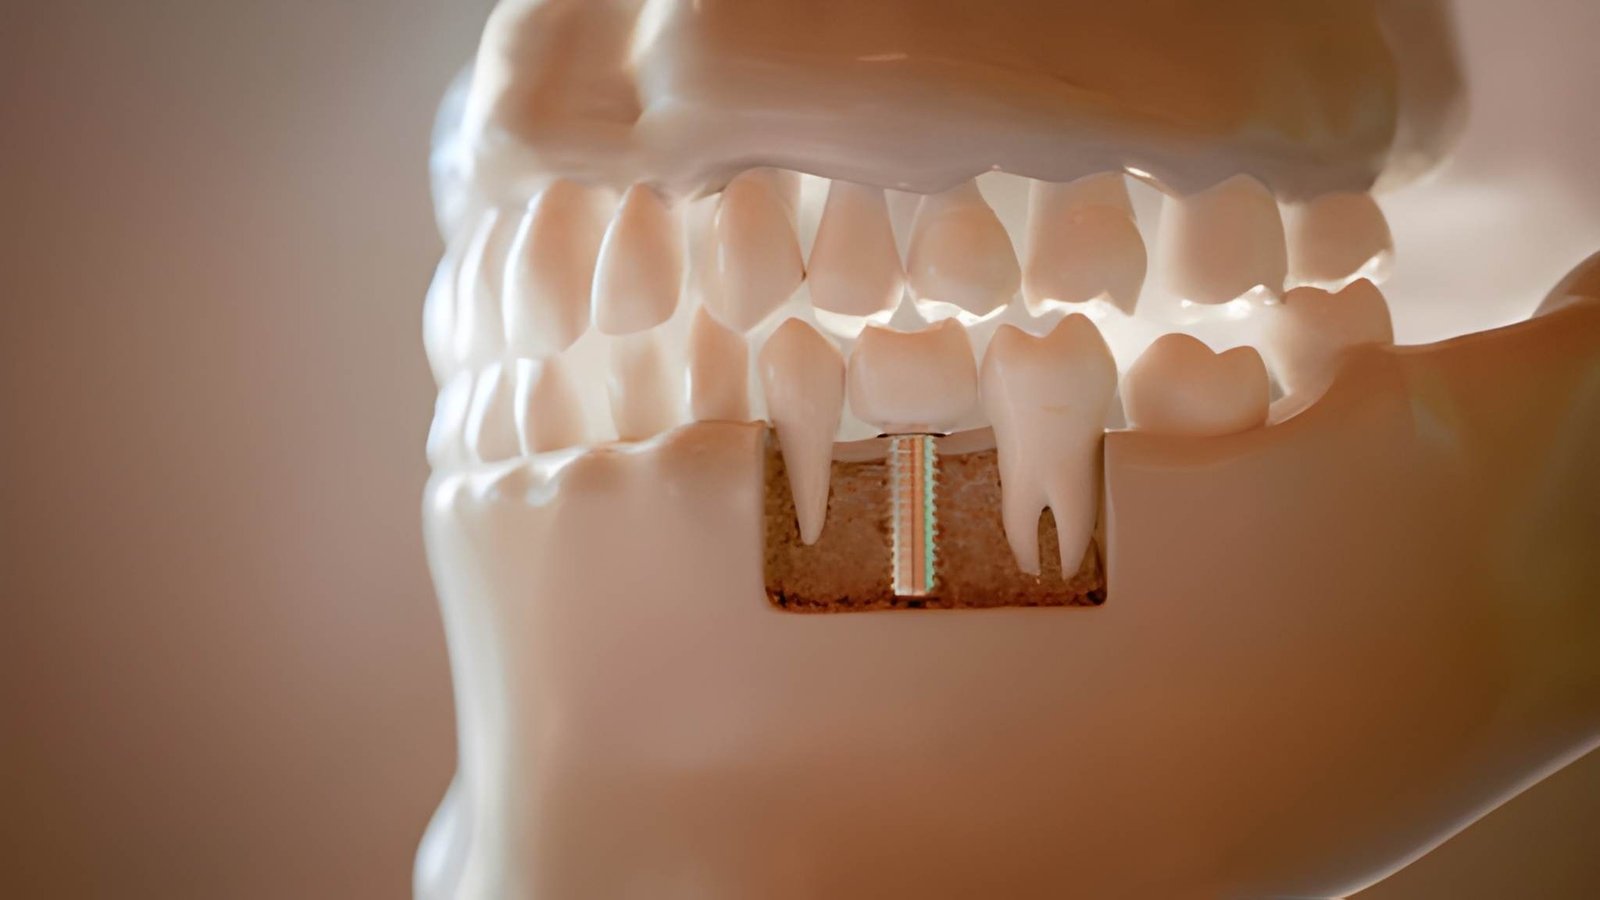

Phase 4: Implant Surgery

During the surgical stage, the titanium post (serving as the artificial root) is inserted into the jawbone. This is a minor surgical procedure performed under local anaesthetic. The surgery usually takes one to two hours per implant. After placement, the gum is sutured around the implant to promote healing.

Phase 5: Healing and Osseointegration

This healing period—known as osseointegration—is when the implant fuses with the jawbone. It is the longest stage, typically lasting three to six months. A temporary crown or denture may be fitted during this time to maintain aesthetics and function. Proper care and hygiene are essential to ensure successful integration.